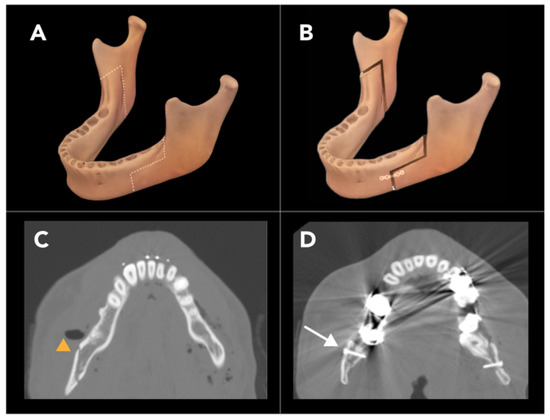

2.1.4. Bilateral Sagittal Split Osteotomy

- Böckmann, R.; Meyns, J.; Dik, E.; Kessler, P. The modifications of the sagittal ramus split osteotomy: A literature review. Plast. Reconstr. Surg. Glob. Open 2014, 2, e271. [Google Scholar] [CrossRef]

- Ylikontiola, L.; Moberg, K.; Huumonen, S.; Soikkonen, K.; Oikarinen, K. Comparison of three radiographic methods used to locate the mandibular canal in the buccolingual direction before bilateral sagittal split osteotomy. Oral Surg. Oral Med. Oral Pathol. Oral Radiol. Endodontol. 2002, 93, 736–742. [Google Scholar] [CrossRef] [PubMed]

- Zeynalzadeh, F.; Shooshtari, Z.; Eshghpour, M.; Zarch, S.H.H.; Tohidi, E.; Samieirad, S. Dal Pont vs Hunsuck: Which technique can lead to a lower incidence of bad split during bilateral sagittal split osteotomy? A triple-blind randomized clinical trial. World J. Plast. Surg. 2021, 10, 25. [Google Scholar] [CrossRef]